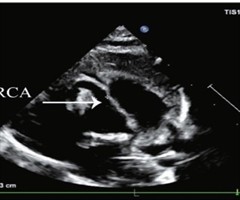

超声诊断胎儿右冠状动脉-右房瘘1例

[中图法分类号]R445.1;R714.5 [文献标识码]B 孕妇29岁,孕29周,孕2产0,因外院产前检查发现胎儿心脏结构异常来我院就诊。自诉孕前尿红细胞增多1年,未行特殊治疗;无心血管疾病家族史及遗传病史。产前常规超声检查:宫内单活胎,...